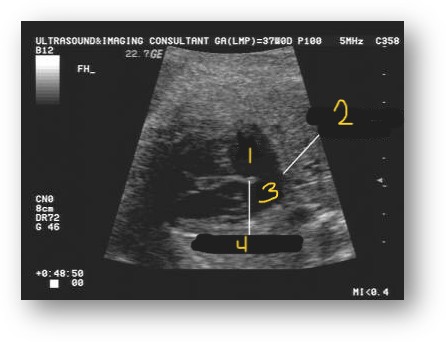

Label this image

Right atrium

Absent septum secundum

Left atrium

Septum primum

ASD